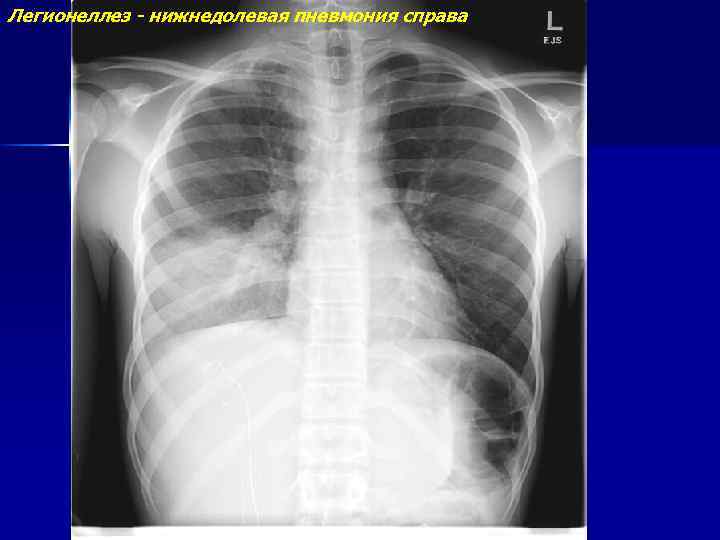

Болезнь легионеров (легионеллез)

Легионеллез - нижнедолевая пневмония справа

Легионеллез - нижнедолевая пневмония справа (продолжение)